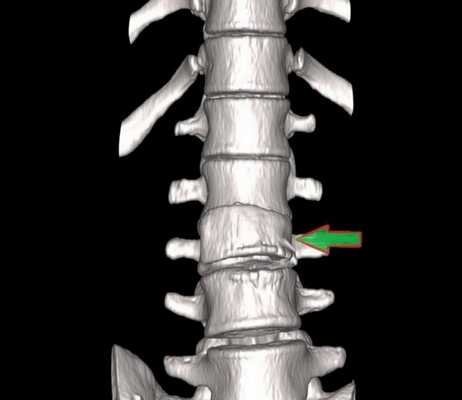

Компрессионный перелом (показан стрелкой) поясничного отдела позвоночника

При развитии патологического процесса возникают структурные нарушения, аномалии формы и размеров морфологических элементов.